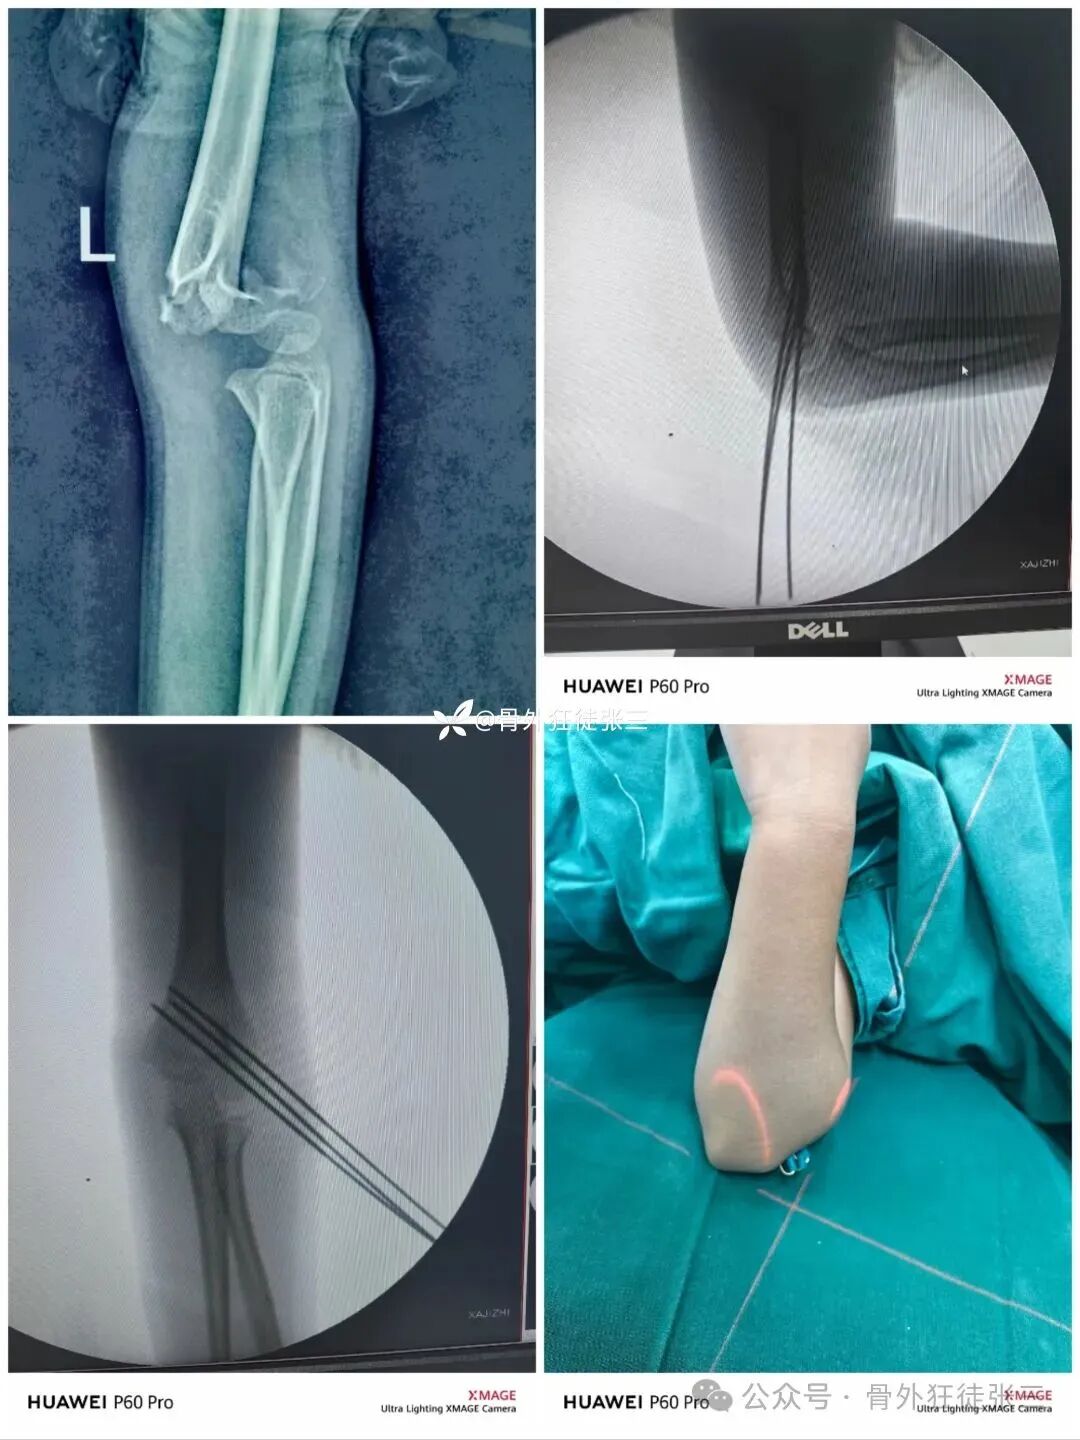

病例8,桡侧三枚针发散固定

病例9,桡侧三枚针,发散固定完美

病例10,桡侧三枚针,发散固定完美

病例11,桡侧三枚针发散固定

6周拔针,关节僵硬

入院康复锻炼1周

12周来院复查

肘关节功能良好